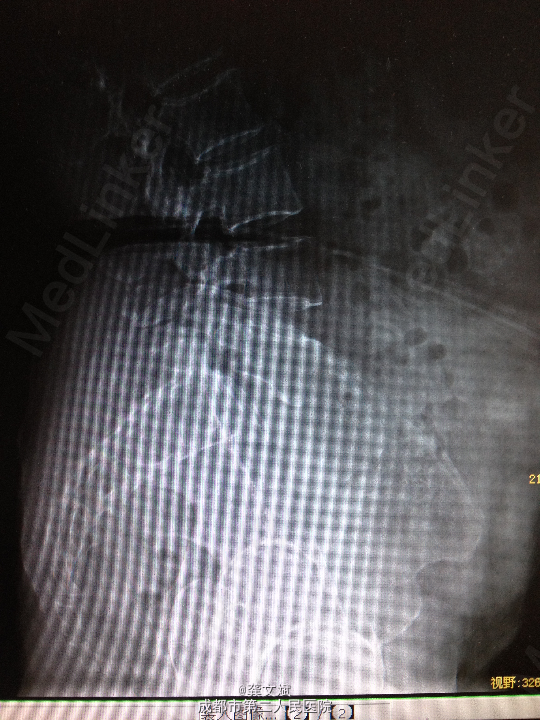

患者女,67岁,因“腰腿痛2月”入院。患者于入院前2月,无明显诱因出现腰腿痛,弯腰时腰痛加剧,无下肢麻木症状及乏力,无大小便障碍。于当地医院行X线提示要5滑脱。

腰5椎体棘突台阶感,腰5水平棘突、椎旁压痛、叩击痛。双下肢肌力、肌张力正常,双侧直腿抬高试验(+)。

诊断:腰5椎体滑脱(I°)、腰5椎体双侧峡部裂 处理:腰5椎间盘摘除、滑脱复位、椎间植骨融合内固定